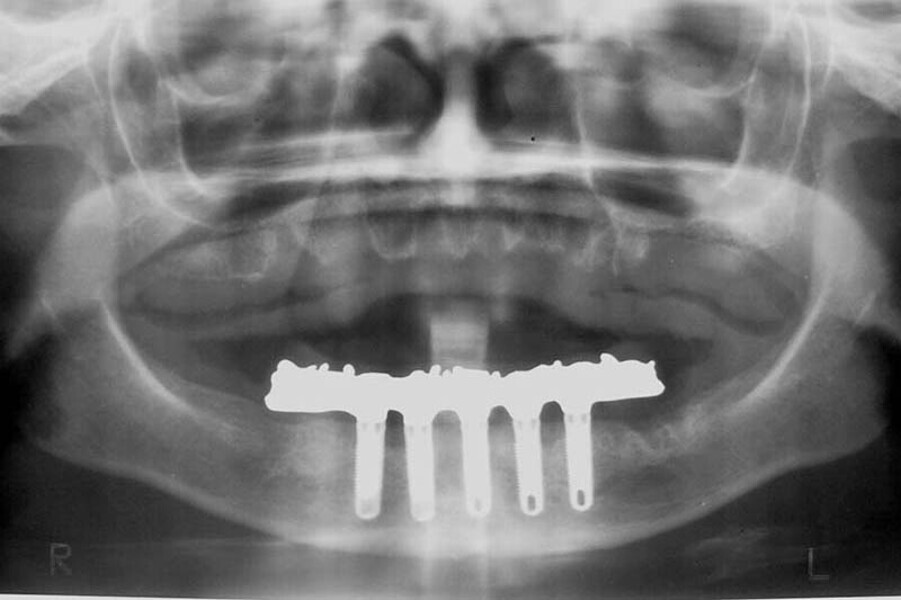

Fig. 7. Rx Pre-operatoria, Prótesis híbrida inmediata con 10 años de evolución y Rx Control a los 10 años.

Fig. 8. Rx Pre-operatoria, Prótesis híbrida inmediata con 10 años de evolución y Rx Control a los 10 años.

Fig. 9. Rx Pre-operatoria, Prótesis híbrida inmediata con 10 años de evolución y Rx Control a los 10 años.